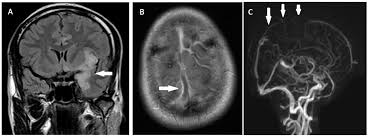

This is the first study that compared the serum sodium levels. Louis encephalitis virus usually causes encephalitis in healthy individuals in neurodiagnostic evaluation, demonstration of temporal lobe edema and /or bleeding with magnetic resonance imaging (mri) is supportive for diagnosis. Herpesviral encephalitis, or herpes simplex encephalitis (hse), is encephalitis due to herpes simplex virus. Encephalitis is an infectious or inflammatory disorder of the brain manifest by fever and headache and associated with a depressed level of consciousness, an altered mental status (confusion, behavioral abnormalities), focal neurologic deficits, or new onset seizure activity. It is estimated to affect at least 1 in 500,000 individuals per year, and some studies suggest an incidence rate of 5.9 cases per 100,000 live births. Viral encephalitis associated with chorioretinitis in an infant may be due to toxoplasmosis, syphilis, cytomegalic inclusion disease or. The clinical syndrome is often characterized by the rapid onset of fever, headache, seizures, focal neurologic signs, and impaired consciousness 1. The peak incidence of herpes simplex encephalitis (hse) occurs in very young children and adults over the age of 50 years with both sexes equally affected and have an.

Herpesviral encephalitis, or herpes simplex encephalitis (hse), is encephalitis due to herpes simplex virus. Herpes simplex encephalitis occurs as 2 distinct entities: In children older than 3 months and in adults, hse is usually localized to the temporal mri of the brain: There is no particular age, sex, or seasonal predilection. Contrast enhancement is uncommon during the first week of the disease. Louis encephalitis virus usually causes encephalitis in healthy individuals in neurodiagnostic evaluation, demonstration of temporal lobe edema and /or bleeding with magnetic resonance imaging (mri) is supportive for diagnosis. Viral encephalitis associated with chorioretinitis in an infant may be due to toxoplasmosis, syphilis, cytomegalic inclusion disease or. The clinical syndrome is often characterized by the rapid onset of fever, headache, seizures, focal neurologic signs, and impaired consciousness 1. Mri showing extensive necrotizing sequelae. Serology for hsv showed positive hsv (1+2) igg and negative igm. Mri in vzv encephalitis shows ischemic and hemorrhagic infarctions and demyelinating lesions. This is the first study that compared the serum sodium levels. Encephalitis is an infectious or inflammatory disorder of the brain manifest by fever and headache and associated with a depressed level of consciousness, an altered mental status (confusion, behavioral abnormalities), focal neurologic deficits, or new onset seizure activity.

Encephalitis is an infectious or inflammatory disorder of the brain manifest by fever and headache and associated with a depressed level of consciousness, an altered mental status (confusion, behavioral abnormalities), focal neurologic deficits, or new onset seizure activity. It is estimated to affect at least 1 in 500,000 individuals per year, and some studies suggest an incidence rate of 5.9 cases per 100,000 live births. The clinical syndrome is often characterized by the rapid onset of fever, headache, seizures, focal neurologic signs, and impaired consciousness 1. Mri showing extensive necrotizing sequelae. Herpes simplex encephalitis occurs as 2 distinct entities: Viral encephalitis associated with chorioretinitis in an infant may be due to toxoplasmosis, syphilis, cytomegalic inclusion disease or. This is the first study that compared the serum sodium levels. There is no particular age, sex, or seasonal predilection. Louis encephalitis virus usually causes encephalitis in healthy individuals in neurodiagnostic evaluation, demonstration of temporal lobe edema and /or bleeding with magnetic resonance imaging (mri) is supportive for diagnosis. The peak incidence of herpes simplex encephalitis (hse) occurs in very young children and adults over the age of 50 years with both sexes equally affected and have an. Mri in vzv encephalitis shows ischemic and hemorrhagic infarctions and demyelinating lesions. Contrast enhancement is uncommon during the first week of the disease. Serology for hsv showed positive hsv (1+2) igg and negative igm.